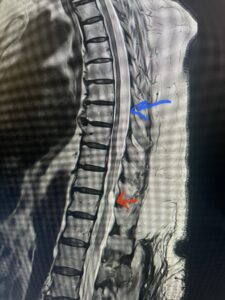

Fig. 1 Sagittal T2-weighted thoracic MRI demonstrating both T10-11 focal intradural arachnoid cyst (red arrow) and larger upper thoracic cyst that appears to extend from T4-T8 (blue arrow).

Fig. 1b Axial T2-weighted thoracic MRI demonstrating spinal cord compression from T10-11 arachnoid cyst (red arrow)

This 67-year-old female presents with progressive heaviness and numbness of the legs and difficulty ambulating. Her right leg was worse than her left. She had right greater than left hip flexor weakness. She was hyperreflexia in her lower extremities. An MRI (Fig. 1) demonstrated an intradural arachnoid cyst at T10-11 with severe spinal cord compression. She also appeared to have an arachnoid cyst above from T4-T8 with anterior displacement and compression of the spinal cord. Because of her severe myelopathy and the findings on MRI the patient underwent laminectomy for surgical decompression of cyst. Intraoperatively the focal arachnoid cyst at T10-11 appeared as a small bubble crushing the spinal cord anteriorly with scarring of the arachnoid with no CSF flow above or below.

The cyst was fenestrated and immediately CSF flow was reestablished. We performed a laminectomy at T6-7 for the upper cyst region which was observed to be more consistent with normal anatomy. We fenestrated the arachnoid. It was felt that the upper level was a secondary phenomenon as a result of CSF flow blockage. Post operatively she had an uneventful course with return of normal strength although she had some residual numbness.